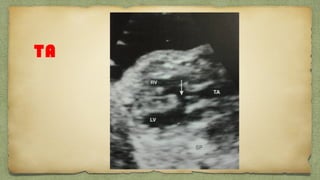

TA